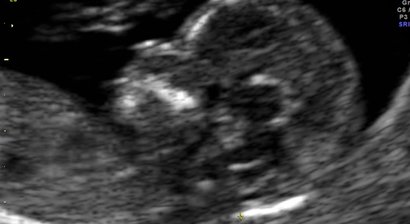

Feindiagnostik/Organscreening 20.-23. SSW

Das Organscreening/Feindiagnostik stellt eine standardisierte Untersuchung dar, bei der definierte Schnittebenen der wichtigsten Körper- und Organstrukturen dargestellt werden. Zusätzlich gilt ein besonderer Augenmerk der fetalen Echokardiographie (Herzuntersuchung).   Damit kann mit...